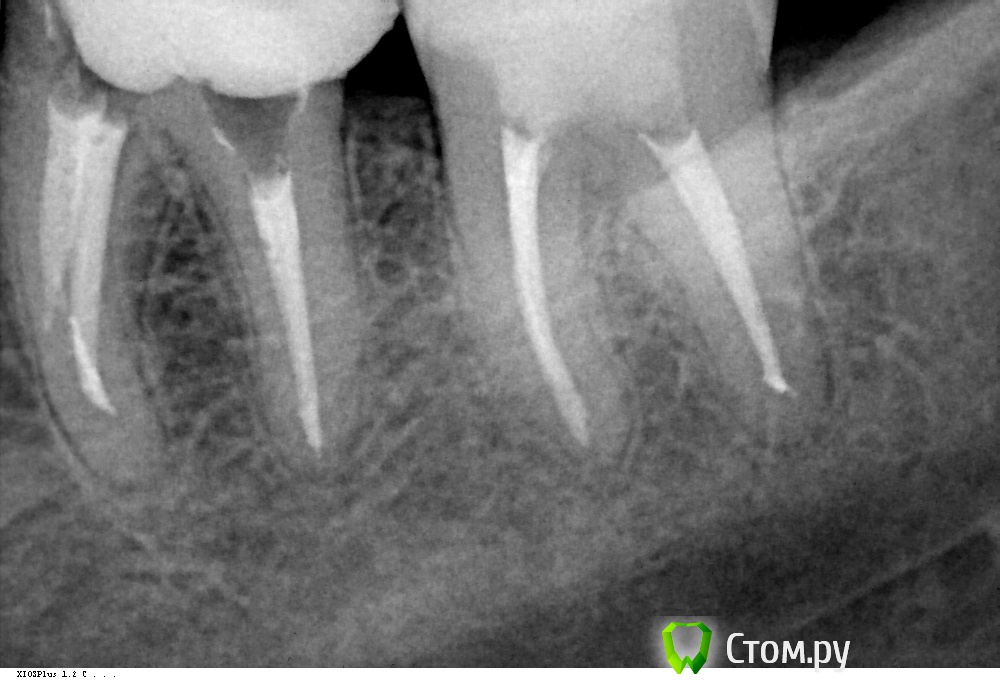

Ирина Сав Опубликовано 28 ноября, 2013 Поделиться Опубликовано 28 ноября, 2013 Добрый день.Беспокоит боль в зубе 3,6.Зуб был депульпирован 16 лет назад. Для удаления нерва закладывали мышьяк, не знаю как название по медицинским правилам.Четыре года назад перелечивали каналы, не помню чем.Сейчас зуб начал разрушаться и я решила поставить коронку. Врач поставил диагноз периодонтит и провел эндодонтическое лечение каналов. Положил лекарство, поставил временную пломбу. Периодически я испытывала ноющую несильную боль. Через неделю поменяли лекарство и так ещё три раза, т.к. была небольшая боль ночью, когда просыпалась. На четвертый раз врач решила, что боль идёт из зуба 3,7 и депульпировала и его. С этого момента боль стала нарастать и становиться более ощутимой. Через неделю, несмотря на боль, врач запломбировала каналы двух зубов горячей гутаперчей. Боль чувствовалась и через обезболивание. После пломбированиия каналов, начались периодические ощутимые боли. На горячее и холодное, а также на надавливание зуб 3,6 не реагирует. Боли возникают иногда спонтанно, бывают еле заметные, бывают ощутимые, но всё время ноющие, не резкие. И по продолжительности тоже разные от 5 мин. до целого дня. Иногда не болит весь день. Но когда ложишься на левую сторону, зуб начинает ныть и проходит, если ложишься прямо. В последнее время четко болит по ночам, боль ноющая , но терпимая. За месяц, который прошел после пломбирования каналов, несколько раз пила найз, т.к. боль длилась весь день и уже изматывала.За этот месяц, несмотря на боль, зуб 3,6 начали готовить к установке вкладки, сняли слепки, мерили готовую вкладку. Раньше спрашивала у врача, не вредно ли целый месяц держать лекарство в каналах зуба, она ответила, что будет хуже , если каналы запломбировать, а они будут болеть. В итоге пломбировали каналы на боль (совсем не сильную и только ночью 5-10 мин., пока засну) и собираются ставить вкладку тоже на боль (но уже ощутимую и сильно беспокоющую).Помогите разобраться, что с зубом 3,6, т.к ощущаю боль именно в нем. Может неправильно пролечены каналы?Снимок зубов 3,6 и 3,7 во вложении. Ссылка на комментарий

IvanK Опубликовано 29 ноября, 2013 Поделиться Опубликовано 29 ноября, 2013 возможно пропущен канал, нужно повторное лечение, по моему мнению Подождем что скажут терапевты. Ссылка на комментарий

Scrabble Опубликовано 5 декабря, 2013 Поделиться Опубликовано 5 декабря, 2013 В 36 ничего такого ужасного не вижу-то есть, заступенились, конечно, и до конца не удалось каналы пройти, но это бывает. Боли начались после манипуляций с 36-или раньше бывало? Ссылка на комментарий

Ирина Сав Опубликовано 6 декабря, 2013 Автор Поделиться Опубликовано 6 декабря, 2013 В 36 ничего такого ужасного не вижу-то есть, заступенились, конечно, и до конца не удалось каналы пройти, но это бывает. Боли начались после манипуляций с 36-или раньше бывало?Да, Боли практически каждый день начались после манипуляций с 3,6.До этого я чувствовала неприятные ощущения в нём где-то раз в полгода - год, непродолжительное время час-два. Ссылка на комментарий

Scrabble Опубликовано 6 декабря, 2013 Поделиться Опубликовано 6 декабря, 2013 Может быть, есть перфорация по большой кривизне корня. Тогда только удалять. 1 Ссылка на комментарий